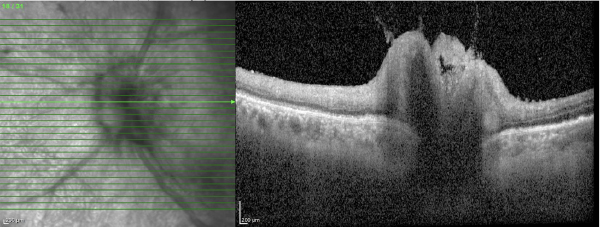

Lymphomatous optic neuropathy (LON) is a rare but vision-threatening manifestation of central nervous system (CNS) lymphoma, characterized by the direct infiltration of malignant cells into the optic nerve. It can occur as a primary process or, more commonly, as a secondary spread from systemic non-Hodgkin’s lymphoma, such as diffuse large B-cell lymphoma (DLBCL). Early diagnosis is critical to preserving vision and life, yet detection remains a significant clinical challenge.

This case report discusses a patient with a history of DLBCL who presented with progressive optic neuropathy despite negative neuro-imaging and cerebrospinal fluid analysis. The case illustrates the limitations of standard CNS surveillance in detecting occult infiltration and highlights the necessity of tissue biopsy for definitive diagnosis.